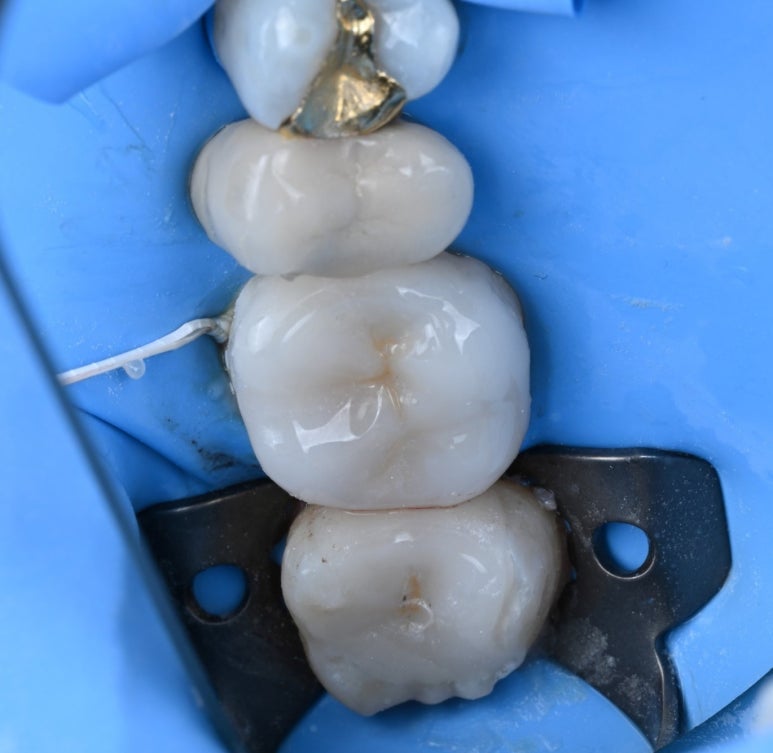

25.11.11 러버댐 장착 후 레진 코팅을 시행한 모습

레진 코팅(Resin Coating)

본을 뜨기 전, 노출된 상아질을

레진으로 얇게 코팅하여 신경을 보호하고

접착력을 극대화합니다.

이 과정을 거치면 치료 후 시린 증상이 현저히 줄어듭니다.